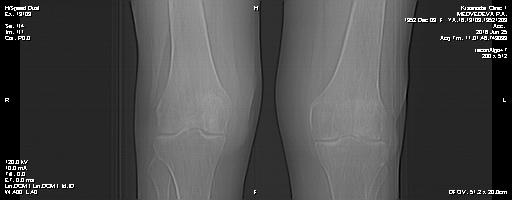

Мне 64 года,житель Краснодара,вот уже на протяжении 4 х лет болят суставы-колени,кисти рук и руки от плеч и предплечья.До 60 лет практически не знала что такое болячки.Ранее занималась спортом в юности-легкой атлетикой,велосипед,лыжи,коньки...а вот теперь порой встать не могу на ноги и поднять руки.И куда не пойду никто точно диагноз поставить не может,от лекарств уже болеть начала печень.Последний год стараюсь не пить ничего,толку все равно нет от них.В октябре 2016 на свой страх и риск поехала в санаторий в Сочи,хотя терапевт и не пускал.При сдаче ан.крови постоянно повышен СОЭ и ревмофактор.Сделали снимок КТ,диагноз поставили-деформирующий остеоартроз 2 степени.Супрапарателярный бурсит.Ввели в коленный сустав дипроспан с новокаином,пока терпимо,а вот левое колено стало сейчас болеть тоже,сделали тоже самое нет улучшений...Дипроспана нет и др.лекарства незнаю какие принимать и что еще делать...никто нас не лечит и даже платные клиники нам уже не по карману,пенсии 10 тыс.рублей,а туда с такими деньгами и делать нечего...помогите,очень хочется еще походить на своих ногах...